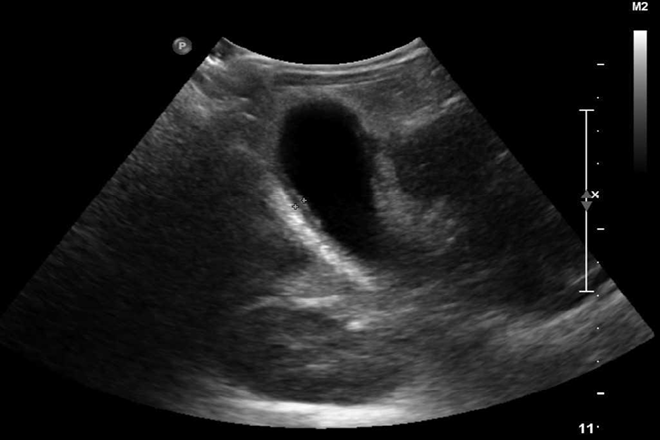

Vesícula en porcelana y carcinoma de vesícula: correlación de diagnósticos por imagen y anatomopatológico El término «vesícula en porcelana» se acuñó en 1929 para describir la decoloración azulosa y la consistencia quebradiza de la vesícula biliar con calcificación extensa de su pared. La calcificación intramural de la vesícula representa el